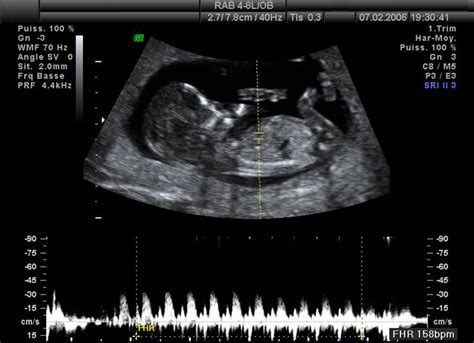

Už počas vnútromaternicového vývinu sa dieťa aktívne pripravuje na prijímanie zvukov a neskôr aj na produkciu reči. Sluch, ktorý je kľúčový pre rečový vývin, sa začína rozvíjať už v treťom mesiaci tehotenstva. Približne od 18. až 20. týždňa tehotenstva je možné pozorovať reakcie dieťaťa na vonkajšie zvukové podnety. Spočiatku vníma tlmené, nízkofrekvenčné zvuky vychádzajúce z matkinho tela - tlkot srdca, prúdenie krvi, šumenie tráviaceho traktu. Tieto zvuky, pripomínajúce tzv. biely šum, sú pre bábätko upokojujúce.

Postupne, okolo 24. týždňa tehotenstva, sa vnútorné ucho prepája s mozgovou kôrou a sluchové schopnosti dieťaťa sa ďalej zdokonaľujú. V tomto období už plod dokáže rozlíšiť hlas mamy a neskôr aj hlasy iných ľudí v okolí. Je dôležité si uvedomiť, že zvuky z vonkajšieho prostredia sú v maternici tlmené plodovou vodou a matkiným telom. Napriek tomu sú však pre dieťa vnímateľné. Hlasné zvuky, ako napríklad hluk strojov alebo koncerty, môžu zvýšiť srdcovú frekvenciu a pohyby plodu, čo naznačuje jeho znepokojenie. Naopak, jemné melódie a upokojujúci hlas rodičov majú na dieťa pozitívny vplyv.

Vývoj sluchového aparátu je pozoruhodný. Už okolo šiesteho týždňa tehotenstva sa začínajú formovať základy uší. V deviatom týždni sa objavujú zárezy na krku plodu, ktoré sa postupne menia na uši. Vnútorné ucho sa spája s mozgovými neurónmi zodpovednými za spracovanie zvuku a v strednom uchu sa tvoria drobné kosti snímajúce vibrácie.

- 16. týždeň tehotenstva: Štruktúra uší je už natoľko vyvinutá, že plod začína detekovať prvé zvuky, najmä tie z matkinho tela.

- 18. - 20. týždeň tehotenstva: Dieťa vníma prvé tlmené zvuky, ktoré sú tlmené plodovou vodou a matkiným organizmom.

- 24. - 28. týždeň tehotenstva: Plod už dokáže jasne reagovať na zvuky zvonka. Hlasné zvuky môžu spôsobiť jemné strhnutie alebo zmenu polohy. Reakcie môžu zahŕňať kopnutie, otočenie alebo zrýchlenie srdcového tepu.

- 30. - 36. týždeň tehotenstva: V tomto období si dieťa vytvára silné spojenie s matkiným hlasom, ktorý po narodení uprednostňuje. Hudba môže mať upokojujúci alebo stimulačný efekt.